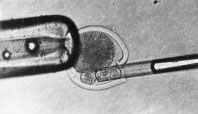

細胞核移植過程1、他們從多位接受試管受孕的大齡婦女體內採集了31個卵子細胞,並將其中的細胞核提取出來。

2、再將這些細胞核注入到年輕婦女的卵子細胞質中。這些捐獻卵子的年輕婦女年齡都在35歲以下,身體健康。從移植的結果看,共有25個“混卵”細胞可以存活。這25個“混卵”細胞與精子相結合後,其中有7個“混卵”細胞形成了初期的胚胎,成功率為28%。此前未經修復的卵子細胞受精成功率僅為3%。